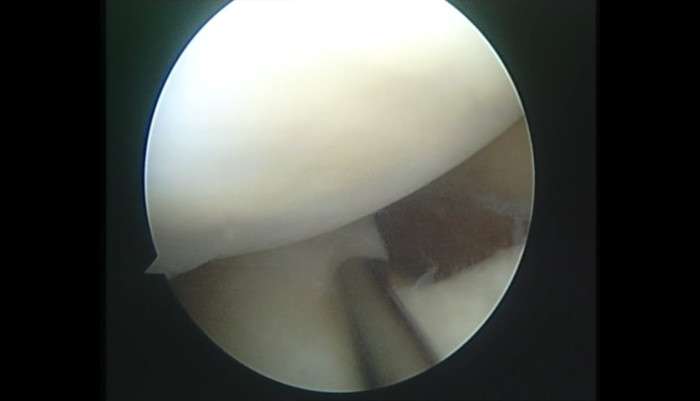

Tibial emintia kırığının erişkinde tam artroskopik tamiri.

Erişkin bir bayan kayakçıda tibial spine kırığının dikiş tekniği ile tamiri. 24 years old female skier with eminentia intercondylaris fracture, suture

lateral meniscus posterior root tear repair (together with radial tear), complex pattern

It is not usual to detect lateral meniscus posterior root tear. This professional athlete has complex posterior tear. Our choice for this complex patt